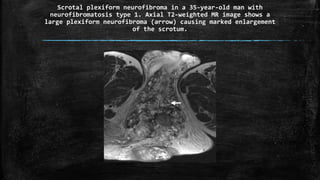

Scrotal plexiform neurofibroma in a 35-year-old man with

neurofibromatosis type 1. Axial T2-weighted MR image shows a

large plexiform neurofibroma (arrow) causing marked enlargement

of the scrotum.

Scrotal plexiform neurofibromain a 35-year-old man with neurofibromatosis type 1. Axial T2-weighted MR image shows a large plexiform neurofibroma (arrow) causing marked enlargement of the scrotum.